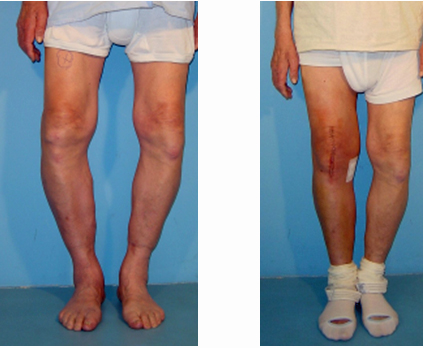

Abb. 3: Begradigung der Beinachse durch den Gelenkersatz.